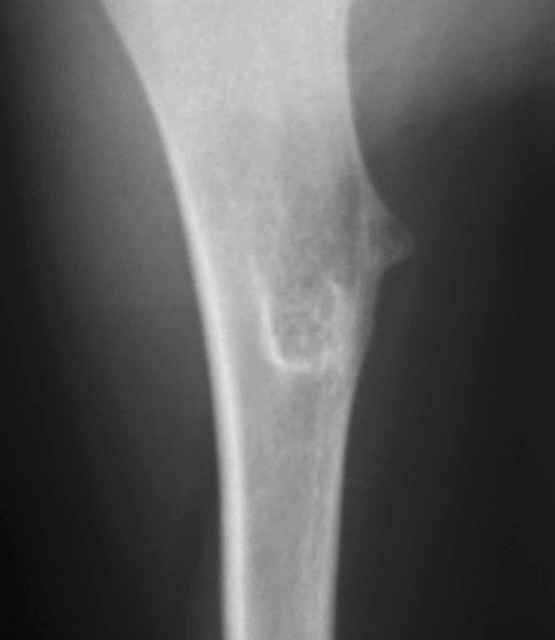

У 12-летнего мальчика образовалась припухлость на верхней трети плеча.

Рентгенобслежование выявило такую картину (см. прикрепленные файлы). Нельзя исключить

энхондрому диафиза плечевой кости. Какую тактику лечения выбрать: экскохлеация или